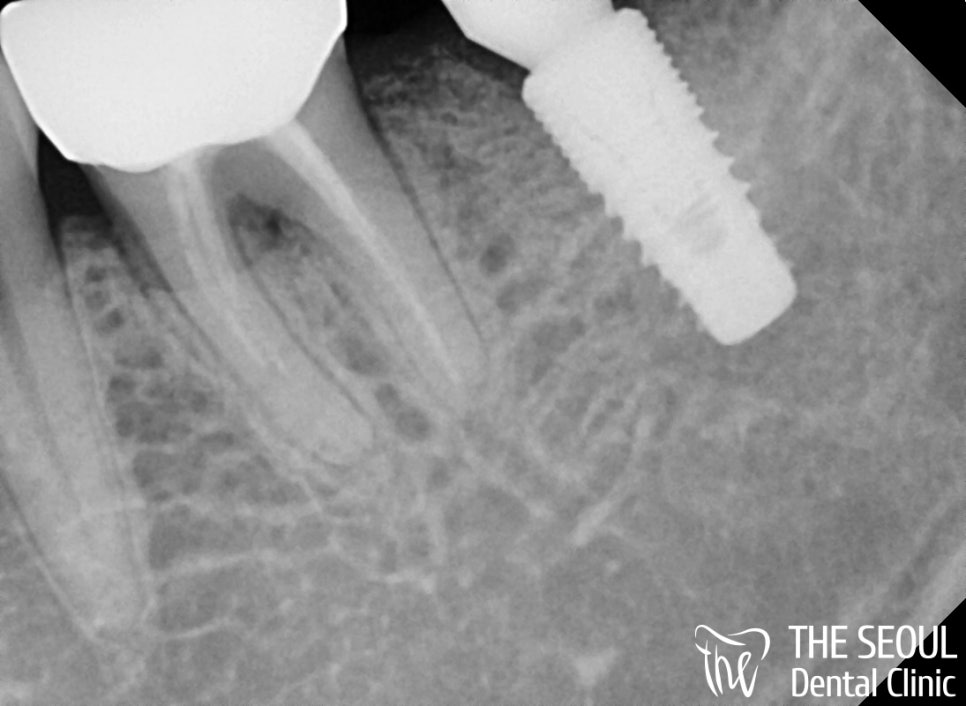

성남치과 에서는 혹여나 파절된 곳이 있는지,

단단하게 결합이 잘 되어 있는지

정밀 검진을 진행했는데요.

다행히 별다른 문제는 발견되지 않았기에

환자분 구강에 어울리는 최종 보철만

제작해 드리면 될 것 같네요^^

구내 사진을 보면 픽스쳐의 방향이

악궁의 형태에 맞게끔 약간 설측으로

심어졌으면 더 좋았을 것 같다는 생각이 들었지만,